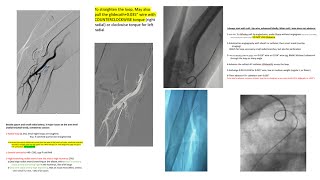

Radial loops- Difficult radial, subclavian and aortic anatomy: step-by-step, cases, perforation

Left EBU/CLS guides manipulations, radial and femoral +Ikari L +Key tips in left coronary engagement

Review of radial catheter techniques: case illustrations + troubleshooting (what is the next step?)

Right coronary engagement: detailed steps, troubleshooting, cases- Amplatz L manipulation-RCA guides